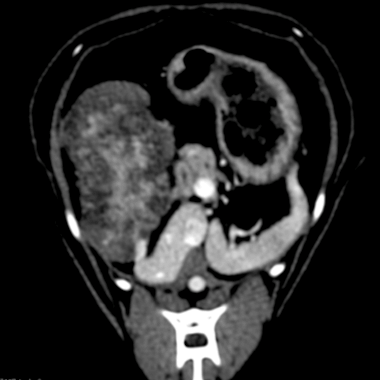

CT(第2病日)

肝動脈尾状葉枝が栄養血管門脈血の流入は確認されず

尾状葉由来5cm大

動脈相

門脈相

CT MIP